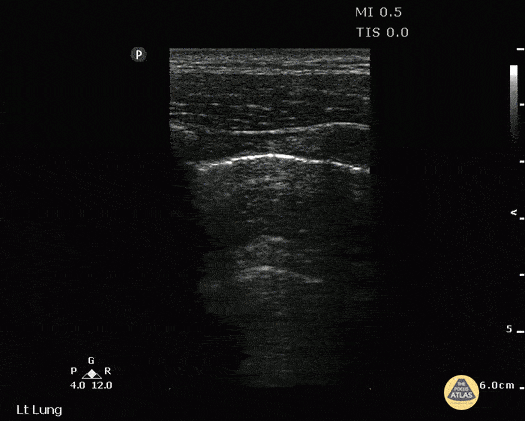

Pulmonary - Double Lung Point Seen in Pneumothorax

A young male presented to ED with stab wound to chest. Upright CXR was normal. POCUS showed double lung point indicative of small PTX. This was monitored without evidence of progression. No intervention was required. Image courtesy of Robert Jones DO, FACEP @RJonesSonoEM Director, Emergency Ultrasound; MetroHealth Medical Center; Professor, Case Western Reserve Medical School, Cleveland, OH View his original post here